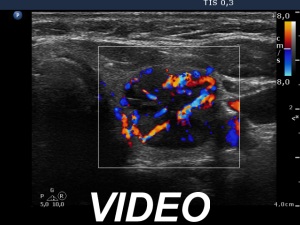

Ultrasonography. The thyroid was echonormal. There were several small discrete partly echonormal, partly moderately hypoechogenic-cystic lesions in the right lobe. The left lobe presented a large nodule composed of peripheral echonormal solid part and a central complex moderately hypoechogenic-cystic area. The hypoechogenic part had a partly chaotic, increased vascular pattern.